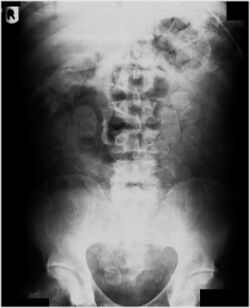

Abdominal X-ray showing swallowed packages of cocaine.

Detection and medical treatment

Routine detection of the smuggled packets is extremely difficult, and many cases come to light because a packet has ruptured or because of intestinal obstruction. Unruptured packets may sometimes be detected by rectal or vaginal examination, but the only reliable way is by X-ray of the abdomen. Hashish appears denser than stool, cocaine is approximately the same density as stool, while heroin looks like air.[11][12]